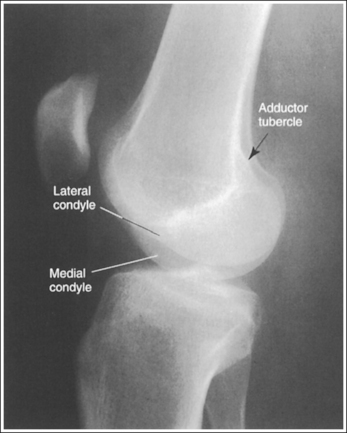

• Distinguishing lateral and medial condyles. The first step you should take when evaluating an image on which the distal condylar surfaces are not aligned is to determine which condyle is the lateral and which is the medial. The most reliable method for identifying the medial condyle is to locate the rounded bony tubercle known as the adductor tubercle. It is located posteriorly on the medial aspect of the femur, just superior to the medial condyle. The size and shape of the tubercle are not identical on every patient, although this surface is considerably different from the same surface on the lateral condyle, which is smooth. Once the adductor tubercle is located, the medial condyle is also identified. Another difference between the medial and lateral condyles is evident on their distal articulating surfaces. The distal surface of the medial condyle is convex, and the distal surface of the lateral condyle is flat.

IMAGE 72

• Effect of knee rotation on femoral condylar superimposition. When an image is obtained that demonstrates one femoral condyle anterior to the other, the patella must be rolled closer to (leg externally rotated) or farther away from (leg internally rotated) the IR for superimposed condyles to be obtained. The first step in determining which way to roll the knee is to distinguish one condyle from the other. As noted, the most reliable method is to locate the adductor tubercle of the medial condyle. When a lateral knee projection is obtained that demonstrates the adductor tubercle and medial condyle posterior to the lateral condyle, the patella was situated too far from the IR (leg internally rotated) (Figure 6-89; see Image 73). When a lateral knee projection is obtained that demonstrates the medial condyle anterior to the lateral condyle, the patella was situated too close to the IR (leg externally rotated) (Figure 6-90; see Image 74).